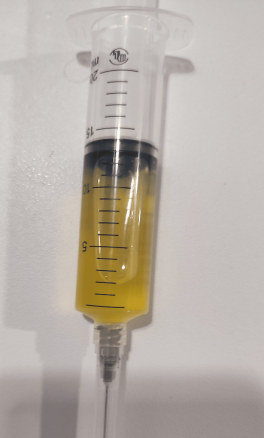

Thoracentesis of pleural fluid resulted exudate and cytology

suggested a (adeno) carcinomatous process originating from upper gastro-intestinal tract.

Figure 2. Pleural effusion sample taken at the emergency unit.